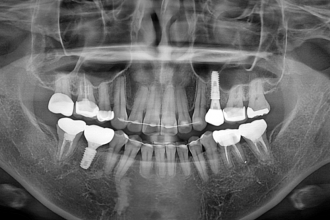

임플란트